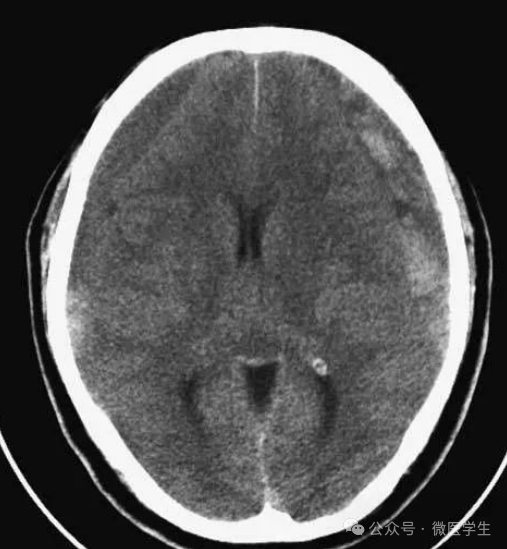

高血压性脑出血:

- 自发性出血;

- 继发于长期高血压及慢性血管病;

- 常见于基底节区、丘脑、脑桥、小脑。

A:占位效应,相邻脑沟、脑池消失;

F:脑出血破入四脑室。

▲

钩回疝:

是当代偿机制不能适应占位性病变时的结果。

基底节区大量高血压性脑出血,破入脑室及蛛网膜下腔,周围水肿,脑干周围空间消失;脑干出血、脑积水。